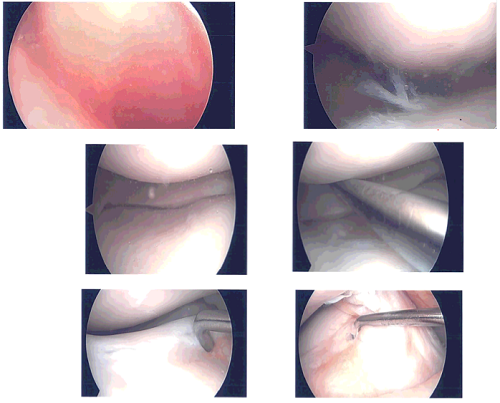

Time-out was called. A lateral entry portal was made. Arthroscopic was inserted and a medial entry portal was made for entry of the instruments. Examination showed a lateral margin fraying of the medial meniscus which was debrided with the use of shaver and Coblation wand.

There was no arthritis of the medial tibiofemoral compartment. Examination of the intercondylar region showed intact ACL. Examination of the lateral tibiofemoral compartment showed tear in the anterior horn of the lateral meniscus, which was debrided with the use of shaver and Coblation wand.

There were no arthritic changes. Examination of the patellofemoral compartment showed grade 1 to grade 2 arthritic changes in the patella, which was cleaned with the Coblation wand. Superior plica was found to be inflamed and was excised with the use of Coblation wand and shaver. Finally, pictures were taken and saved.